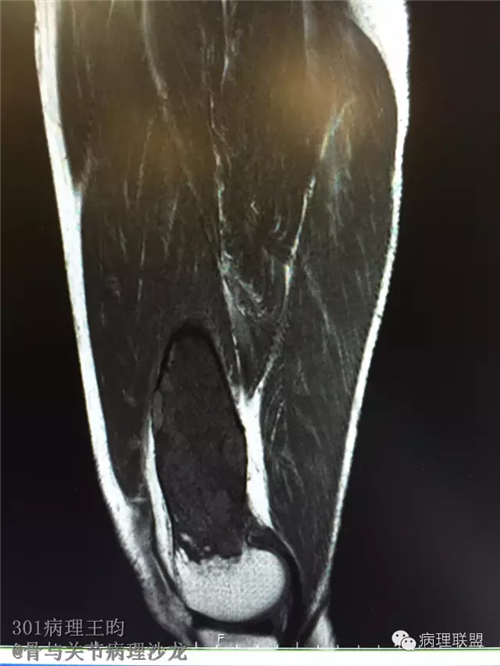

右股骨髓内高分化低级别骨肉瘤or骨纤维异常增殖症(Fibrous Dysplasia)?

男,36岁,活动后疼痛,发现右股骨远端肿瘤。